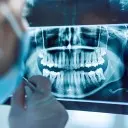

W tym wydaniu m.in: skojarzone leczenie dużej zmiany okołowierzchołkowej, miejsce nimesulidu w leczeniu bólu poekstrakcyjnego, materiał Activa BioActive, odbudowa braków międzyzębowych w szczęce, Warsaw Dental Medica Show 2025.